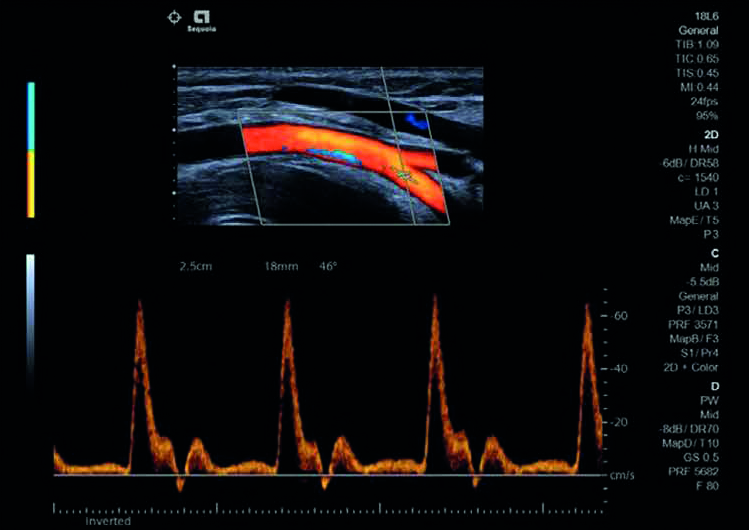

Visualizza un tracciato Doppler pulite e chiare grazie a Doppler TEQ. Scala, guadagno e linea di base vengono regolati automaticamente con funzionalità complete di post elaborazione.